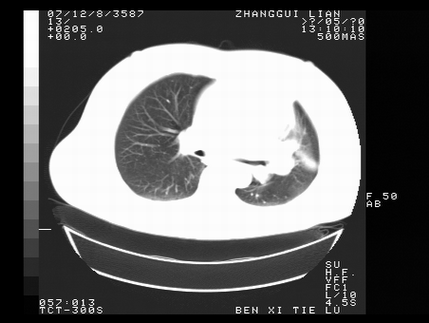

标题: CT10817:女,46,胸疼,无其他病史 [打印本页]

标题: CT10817:女,46,胸疼,无其他病史

左侧上纵隔旁团块影,部分植入纵隔,与纵隔界限不清,另:左肺门明显见团块,气管隆突前方见肿大淋巴结。考虑:左上肺纵隔型肺癌伴左肺门及纵隔淋巴结转移!

首先考虑左侧中央型肺癌伴阻塞性肺炎、纵隔内、弓旁淋巴结转移可能性大(纵隔窗调的欠佳)

1左上肺中心型肺癌伴左肺上叶不张2主动脉弓旁淋巴结转移3左下肺炎症

1 左侧中央型肺癌伴阻塞性肺炎 2 左肺门及纵隔淋巴结转移!3两侧胸腔及心包积液.

左侧胸廓塌陷,纵隔向左侧移位,左上肺不张。